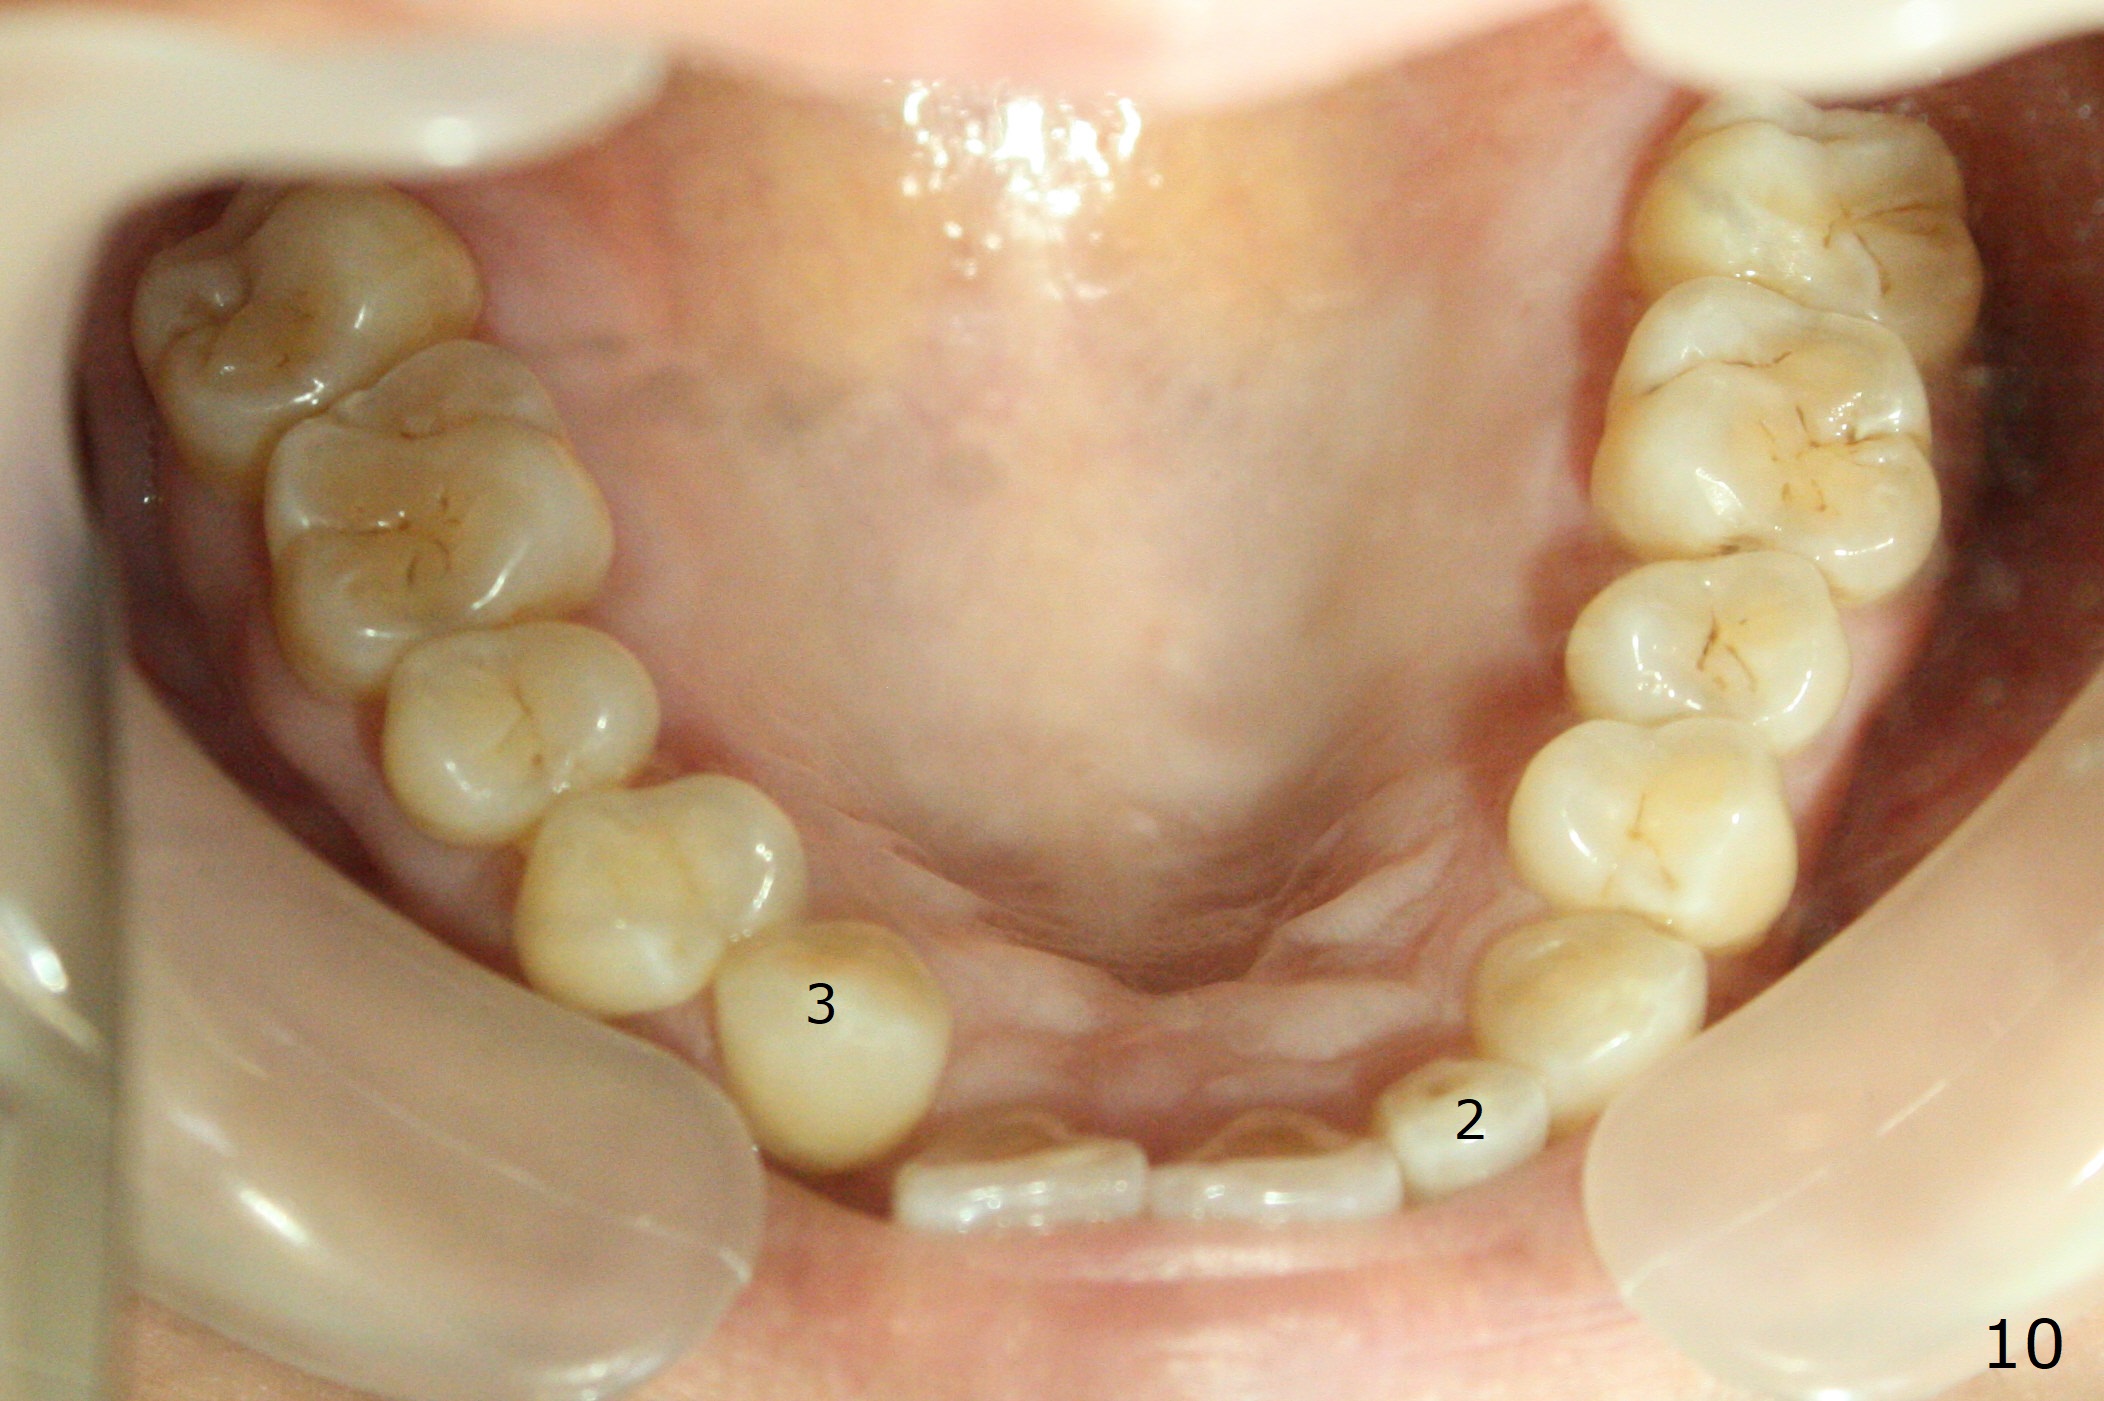

A 54-year-old woman (dento-phobic) will return for banding and bracketing 1.5 months post UR2 extraction with socket preser-vation. Lip strain is absent or minimal(Fig.1). The upper dental midline deviates to the right (Fig.2). Profile is within normal limit (Fig.3). UR3 is in cross bite (Fig.4). Cephalmetric X-ray apparently shows normal profile (Fig.5). Occlusion appears to be Class II in canine and molar (Fig.7,9, Class II Division II Malocclusion). The upper and lower dental midlines mismatch (Fig.8). UL2 is a peg lateral (Fig.10), while the lower anteriors are crowded (Fig.11). Arch wire sequence is conducted and let the timid patient decide whether the 2nd part of treatment should restore ideal occlusion with UR2 implant and UL2 veneer or simply close diastemata. Take PAs for the anteriors prior to banding to follow up root resorption during treatment.